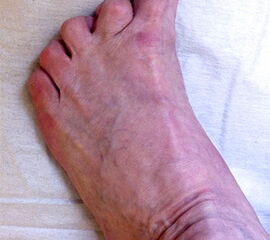

Radiologische Diagnostik

11"> Der Hallux varus Winkel  <a class=11" title="Der Hallux varus Winkel 11" srcset="/assets/images/2/4-vk3bypbg5s5x7zc.jpg 1x, /assets/images/3/4-aax2sd1hrpnrvrb.jpg 1.452x" width="270" height="240" loading="lazy">

Abbildung 3

Die bildgebende Diagnostik hilft bei der Klärung der Ätiologie und des Ausmaßes der Fehlstellung. Hierzu sind Röntgen­aufnahmen im Stand in mindestens zwei Ebenen unter Belastung des Fußes erforderlich. Mit Hilfe der belasteten Röntgenaufnahmen wird der Hallux-varus-Winkel, d. h. den Winkel zwischen der Achse der Grundphalanx der Großzehe und der Achse des ersten Mittelfußknochens bestimmt, sowie etwaige Rotationsfehlstellungen des 1. Strahls verifiziert. Eventuelle knöcherne Fehlanlagen bei kongenitalen Deformitäten können hierdurch ebenfalls verifiziert werden.

Weitere Beurteilungskriterien sind:

• degenerative Veränderungen des MTP I

• Kongruenz des MTP I- Gelenkes

• Form und Stellung des Mittelfußköpfchens I

• Ausprägung der Pseudoexostose.

• PASA-Winkel, d. h. der periphere Artikulationswinkel des Großzehengrundgelenkes.

Zur Klärung der Ätiologie wird der intermetatarsale Winkel zwischen Os metatarsale I und II bestimmt. Ist dieser kleiner als 5° oder gar negativ, ist eine Varusstellung der Großzehe oft die Folge.

Am Röntgenbild des belasteten Fußes bestimmt man die Lage der Sesambeine zum 1. Mittelfußköpfchen.

Anhand der Röntgenaufnahme lassen sich die Folgen einer eventuellen Voroperation bestimmen, wie z. B. die Stellung des ersten Mittelfußköpfchens, des ersten Metatarsale nach Korrekturen der Achse bei einer Hallux-valgus-Operation. Mitunter bestehen Nekrosen des Mittelfußköpfchens oder eine übermässige Resektionen der Pseudoexostose. Auch die Länge des 1. Metatarsale kann von Interesse sein, z. B. nach einer Lapidusarthrodese (Johnson 1994).